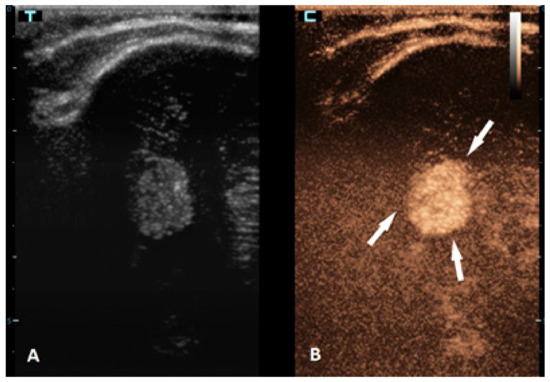

Figure 4.

A 6-month-old premature boy with an accidentally detected small lesion in the 4th ventricle. (A) The transverse reference grayscale ultrasound image through the left mastoid fontanelle. (B) The transverse CEUS image of the 4th ventricle demonstrates avid arterial and venous enhancement of the lesion (arrows). Findings were suggestive of choroid plexus papilloma; subsequent brain MRI scans confirmed benign aetiology of the lesion.